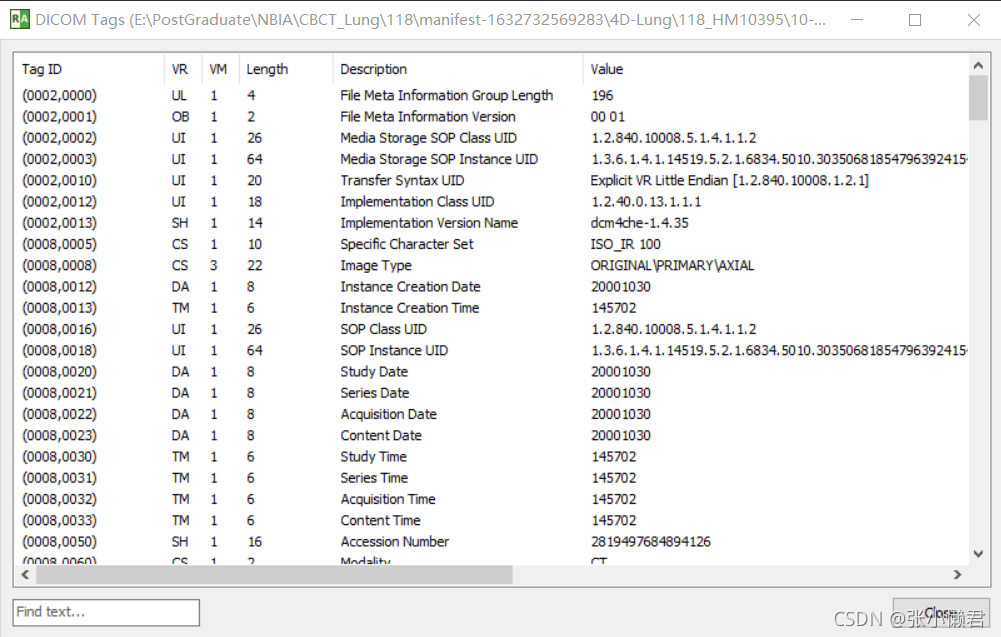

使用软件RadiAnt(RadiAnt DICOM Viewer | ZH (radiantviewer.com))读取DICOM文件信息。

点击 “A”标志的下拉按钮,点击“ show DICOM tag”

下一部分再来学习DICOM tag。

数据元

一个数据元主要由标签(Tag),值类型(VR,Value Representation),数据值长度(Length),值域(VF,Value Field)几部分组成。

①标签Tag:4字节无符号整型,由组号和元素号组成,是数据元的唯一标识码,文件中Tag标签有大约2000个,我们只需要了解常用的Tag即可。

0002组描述设备通讯

0008组描述特征参数

0010组描述患者信息

0028组描述图像信息参数,上图的表格就是Tag组号0028的数据元信息。

Tag号:0002,0010,决定数据元素的传输方式,VR是显式还是隐式。

Tag号:7fe0,0010对应像素数据开始的地方。

②值类型VR:2字节字符串,是数据元素的数据类型。VR有27种

③数据值长度L:2字节或4字节无符号整数,具体长度取决于传输语法,表示数值的长度。

④值域VF:表明数据元素的值。